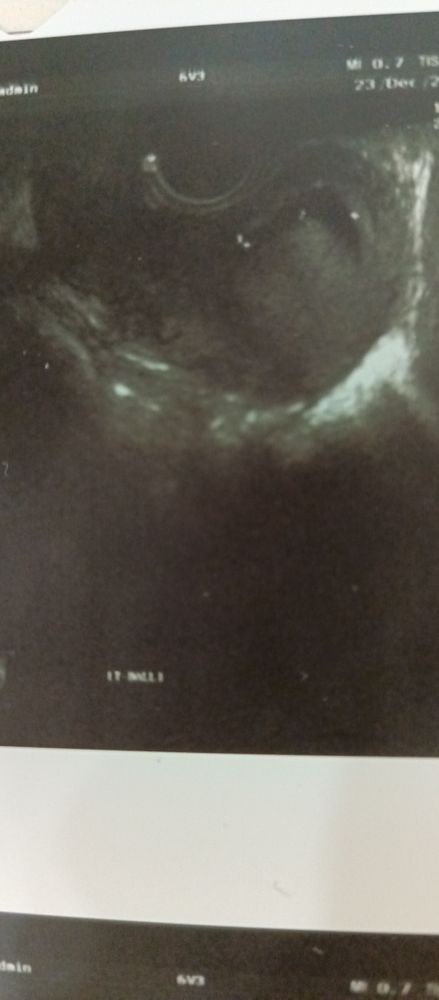

УЗИ, КТГ, доплерВсем привет. Срок 8 недель, ретамниальная гематома 23*8мм. Недели 2 назад была гораздо меньше. И была ретрохориальная. Очень переживаю, так как и не выходит, и не уменьшается, а наоборот. У кого-то было такое?

Гематома которая на фото высоко находится, поэтому она выйти не может, это по сути небольшая отслойка плодного яйца, раз увеличивается, значит, там немного подкравливает.